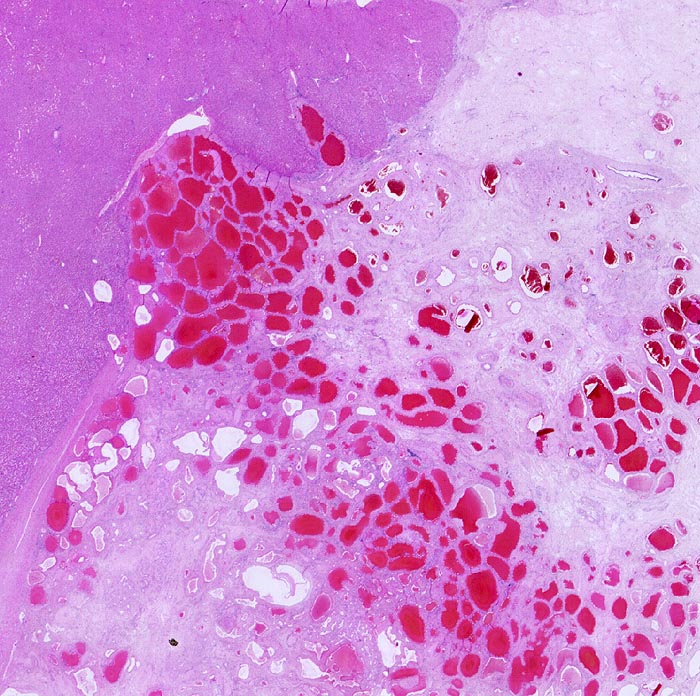

PathoPic ID 899 - Kavernöses Hämangiom

Kavernöses Hämangiom

benigner Tumor

Leber

Leber, Gallenwege, Pankreas

Tumor aufgebaut aus ektatischen Gefässen und Fibrosezonen. Scharfe Begrenzung zum Leberparenchym.

Tumordurchmesser 10cm.

Histologie

Scan